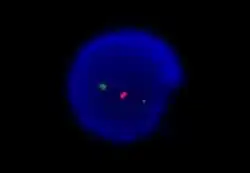

Иммунофенотипирование

Иммунофенотипирование лимфоцитов методом проточной цитометрии обязательно для подтверждения диагноза. Высокочувствительная проточная цитометрия позволяет обнаруживать одну злокачественную клетку на 10 000 нормальных лейкоцитов[15]. В качестве диагностического материала обычно используется периферическая кровь. Для клеток ХЛЛ характерен аберрантный иммунофенотип: одновременная экспрессия (коэкспрессия) Т-клеточного маркера CD5 и В-клеточных маркеров CD19 и CD23[14]. Количество В-клеточных маркеров CD20, CD79b и мембраносвязанных иммуноглобулинов IgM и IgD понижено по сравнению с нормальными В-клетками[3]. В дополнение к этому выявляется клональность. Диагноз ХЛЛ также может быть установлен на основании данных иммуногистохимического исследования биоптата лимфатического узла или селезёнки.

Интерфазная FISH при хроническом лимфоцитарном лейкозе не требует применения митогенов и отличается большей чувствительностью. При анализе используют локус-специфичные зонды, позволяющие выявлять наиболее распространённые хромосомные перестройки (как правило делеции). Этот метод позволяет детектировать хромосомные мутации в более чем 80 % случаев хронического лимфоцитарного лейкоза[16].